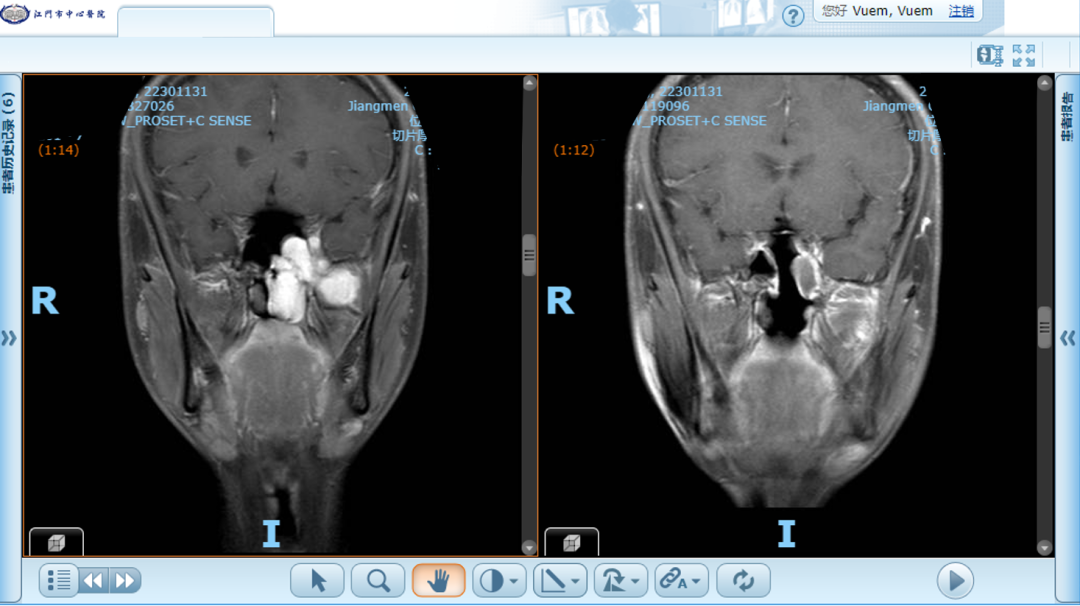

鼻咽纤维血管瘤术前(左)、术后5个月(右)